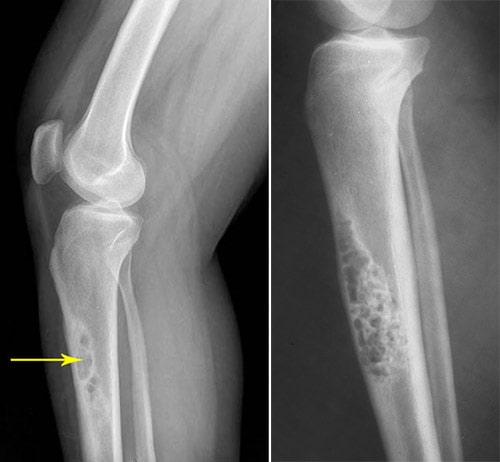

Telangiectatic Osteosarcoma

General Information Telangiectatic osteosarcoma is a variant of an intramedullary high grade osteosarcoma. Accounts for 3% of osteosarcomas Telangiectatic osteosarcoma is extremely lytic on X-rays. It demonstrates very little osteoid production. It is characterized by...